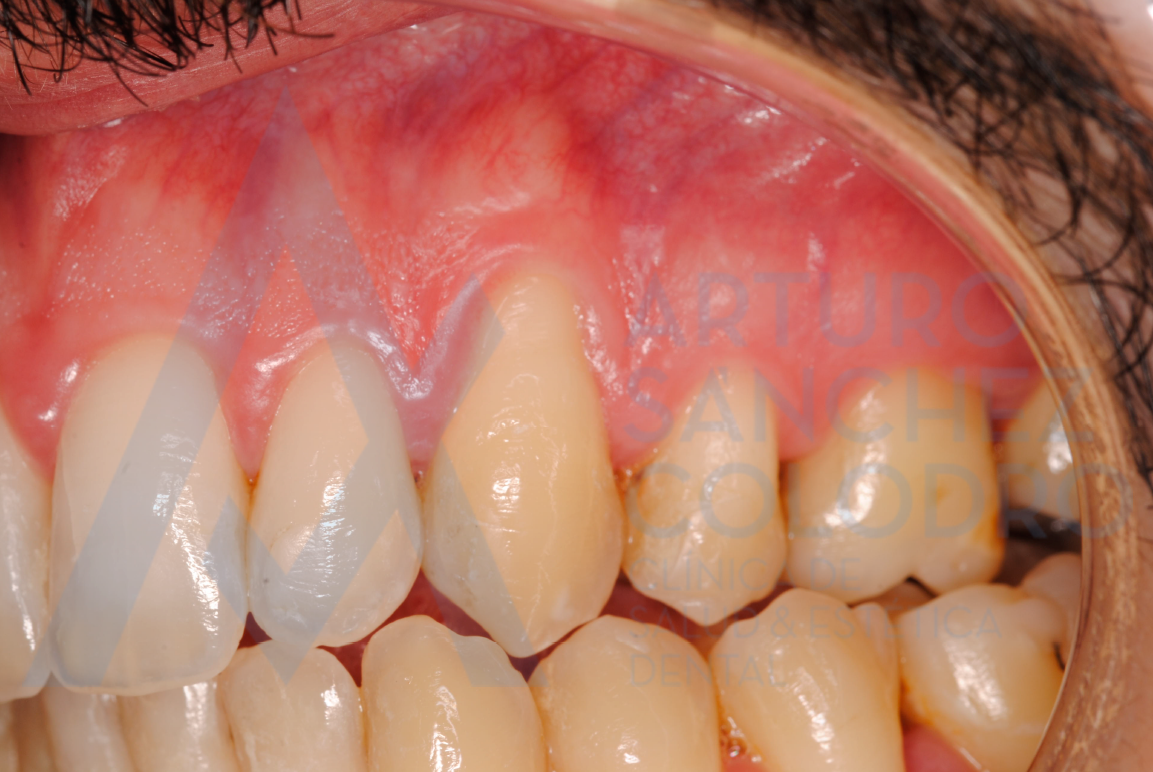

- Injerto de tejido conectivo libre desepitelizado de paladar + Tunelización para colocación MB Mucogain.

Tras la cirugía mucogingival realizada por el Dr. Arturo Sánchez Colodro en la primera parte de la boca (paciente aún en fase de tratamiento):